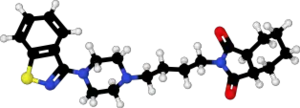

| 3D model (JSmol) | |